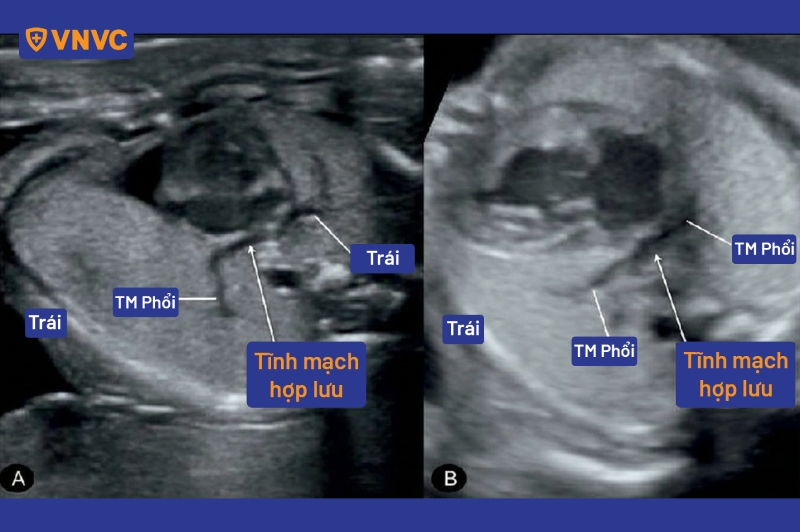

- Siêu âm tim: Đây là kỹ thuật phổ biến nhất để xác định nguyên nhân gây tím tái bẩm sinh. Chẩn đoán được xác lập dựa trên các tiêu chí:

- Không tìm thấy các kết nối bình thường của tĩnh mạch phổi vào tâm nhĩ trái.

- Phát hiện ống thu nhận tĩnh mạch chung, tĩnh mạch dọc, tĩnh mạch chủ trên và tĩnh mạch vô danh giãn lớn (trong thể trên tim).

- Phát hiện ống thu nhận đi xuống kết nối với hệ tĩnh mạch cửa hoặc tĩnh mạch gan, kèm giãn tĩnh mạch chủ dưới (trong thể dưới tim).

- Xác định kết nối trực tiếp giữa hệ tĩnh mạch phổi với tâm nhĩ phải hoặc xoang vành (trong thể tại tim).

- Tình trạng giãn nhĩ phải, thất phải và luồng thông liên nhĩ từ phải sang trái hiện diện trong tất cả các thể.

- Siêu âm Doppler giúp ước tính áp lực động mạch phổi và đo lưu lượng dòng máu qua các tĩnh mạch bất thường.